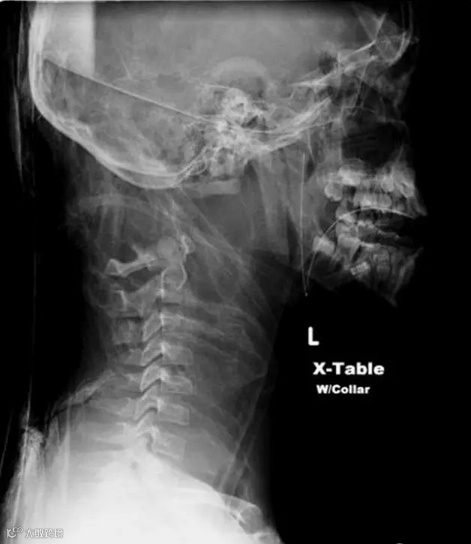

外力导致身体和头分开是我们最熟悉的斩首方式,但是其实还有更有趣少见的体内断头。体内斩首的意思是人的头骨和脊椎分开,但是身体和头还是连在一起的。通常是因为遭遇意外或头部受到重击。像是上吊的绞刑就是利用体内断头的方式确保罪犯死得很快。